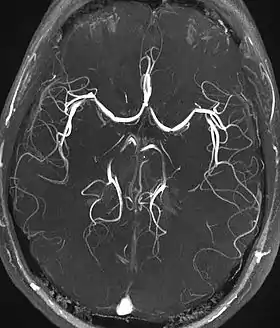

تصوير الأوعية بالرنين المغناطيسي (بالإنجليزية Magnetic resonance angiography (MRA)) هُوَ مَجموعة مِن التِّقنيات القائِمة عَلى التصوير بالرنين المغناطيسي (MRI) لِتَصوير الأوعية الدموية.[3][4][5] يُستخدم تَصوير الأوعية بالرنين المغناطيسي لإعطاء صُور الشرايين (والأوردة الأقل شيوعاً) مِن أجل تَقييمها كالتضيق (تضييق غير طبيعي)، انسداد، تمدد الأوعية الدموية (توسع جدار الوعاء، في خطر التمزق) أوأي تشوهات أخرى. وغالباً ما يُستخدم لِتقييم شرايين الرقبة والدماغ، والشريان الأورطي الصدري والبطني، والشرايين الكلوية، والساقين (وغالباً ما يشار إلى الفحص الأخير باسم "الجريان").

(TOF MRA)أو تدفق الأوعية الدموية، يستخدم وقت صدى قصير وتدفق التعويض لجعل الدم المتدفق أكثر إشراقا من الأنسجة الثابتة. كما يدخل الدم المتدفق المنطقة التي يجري تصويرها وشهدت عددا محدودا من نبضات الإثارة بحيث تكون غير مشبعة، وبالتالي يعطيها إشارة أعلى بكثير من الأنسجة الثابتة المشبعة. وبما أن هذه الطريقة تعتمد على تدفق الدم، فإن المناطق ذات التدفق البطيء (مثل تمدد الأوعية الدموية الكبيرة) أو التدفق الموجود على TOF قد لا يكون مرئيا بشكل جيد. وهو الأكثر شيوعا في الرأس والرقبة ويعطي دقة عالية في الصور.